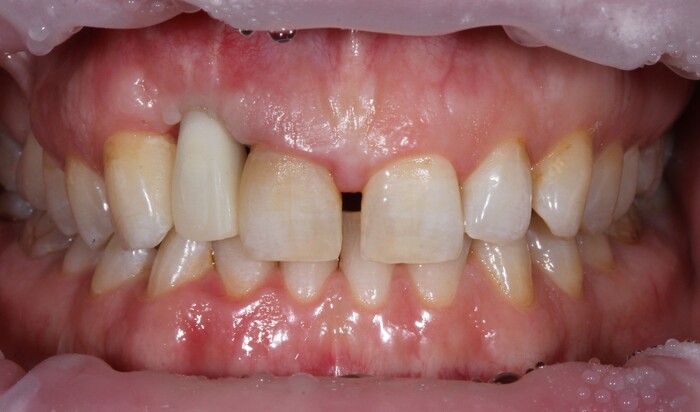

Далее проведена пластика десны, снова два месяца ожиданий и установка временной коронки:

Ну, такое, согласен, но это начало.